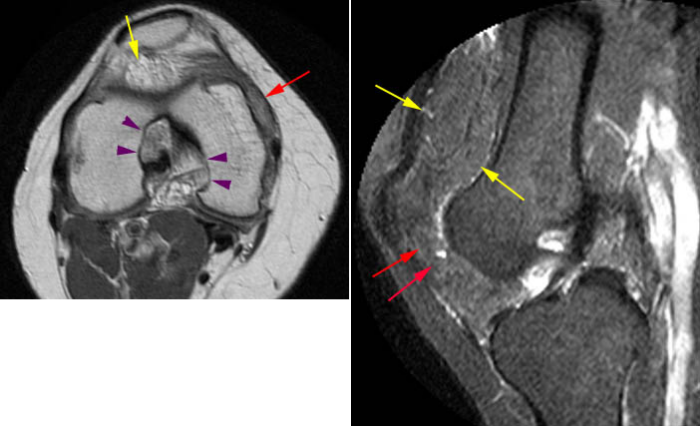

Рисунок 3. Древовидная липома коленного сустава: желтыми стрелками обозначено древовидное разрастание ткани с сигналом, идентичным жиру во всех последовательностях. Также отмечается разрастание синовиальной оболочки без присутствия жировой ткани (красная стрелка) — следствие хронического синовита.

Рисунок 4. Арборесцентная липома колена у женщины с ревматоидным артритом (желтые стрелки). Липома в данном случае сформирована более крупными «дольками» и имеет округлую форму, которая позволяет спутать ее с объемным образованием. На снимках также видно не соответствующее сигналу от жира разрастание синовии — хронический синовит или фиброзный паннус. Фиолетовые стрелки указывают на участки костно-эрозивных изменений — частая находка у пациентов с хроническим артритом.

МРТ-сканы демонстрируют участки округлой формы или в форме листа дерева, выступающие внутрь синовиальной оболочки. МР-сигнал соответствует сигналу от жировой ткани во всех последовательностях. Если вводится гадолиниевый контрастный агент, он накапливается в хронически воспаленной синовиальной оболочке, но не в жировой ткани.

Участки пролиферации образуют конгломерат «ворсинок» или «листочков», которые могут быть более крупными и заметными, или мелкими. Обычно жировая пролиферация диффузная, но может образовывать ограниченный участок, напоминая новообразование.